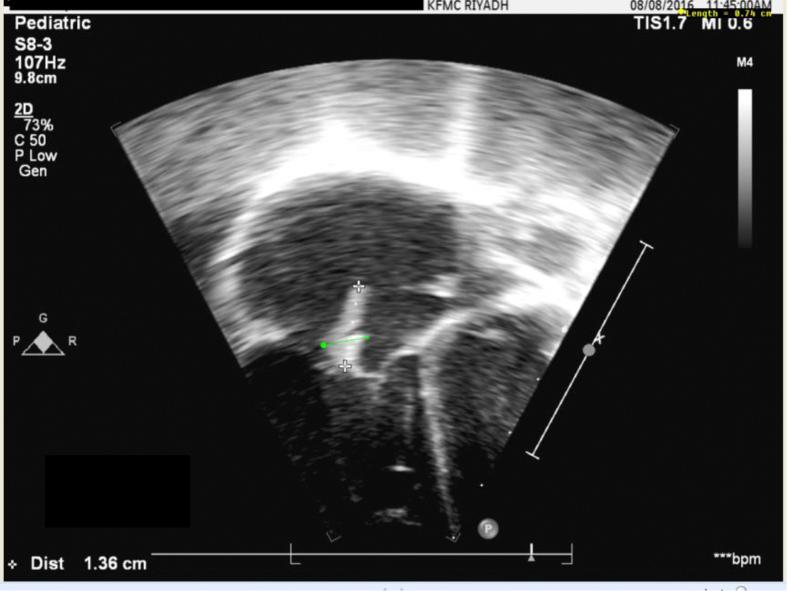

The majority of CA-MRSA infections present as skin and soft tissue infections such as abscesses or cellulitis. However, CA-MRSA can cause invasive infections such as joint infections, necrotizing pneumonia or septicemia. Here we describe five cases with CA-MRSA bacteremia complicated with osteoarticular infection, necrotizing pneumonia, and infective endocarditis. We report these case series to outline the spectrum of invasive CA-MRSA diseases and to demonstrate clinical outcome. Early proper intervention with regular revisiting the empirical treatment based on local susceptibility data is crucial. More data on the risk factors for acquiring and spread of CA-MRSA in children are required.

大多数社区获得性耐甲氧西林金黄色葡萄球菌(CA-MRSA)感染表现为皮肤和软组织感染,如脓肿或蜂窝织炎。然而,CA-MRSA可引起侵袭性感染,如关节感染、坏死性肺炎或败血症。在此,我们描述了5例CA-MRSA菌血症合并骨关节感染、坏死性肺炎和感染性心内膜炎的病例。我们报告这些病例系列,以概述侵袭性CA-MRSA疾病的范围并展示临床结果。基于当地药敏数据定期重新评估经验性治疗进行早期适当干预至关重要。还需要更多关于儿童获得和传播CA-MRSA的危险因素的数据。